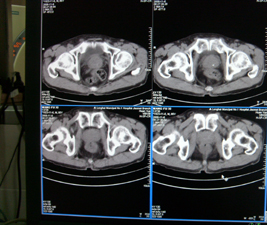

前列腺癌术后10余年,复查有无复发,请指教,图像做得不好,还望包涵

膀胱内可见占位,建议膀胱镜观察

连续看还是前列腺的病变,考虑复发.

前列腺增大,向上突入膀胱内,结合病史考虑前列腺癌复发可能。

图像太小,左侧膀胱壁似见不规则突起,前列腺突入膀胱,建议膀胱镜检查及前列腺增强检查。